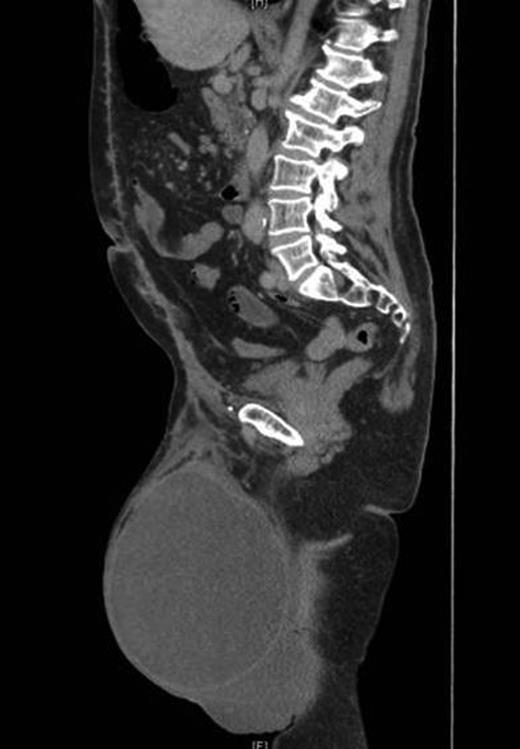

A contrast-enhanced computed tomography (CT) scan revealed the hernia sac containing most of the colon and small bowel with only the rectum, proximal jejunum and duodenum lying within the abdomen (Fig. 2). Preoperative anaesthetic assessment was completed and the patient was admitted to hospital 2 days preoperatively for bowel preparation. After a midline laparotomy, attempts at reduction were not successful even after dividing the inguinal ligament. Reduction in hernia contents was possible only after completely dividing the lower end of the left rectus abdominis muscle. The hernial sac was then dissected and resected. Then, component separation technique was performed laparoscopically using the same balloons used for total extra peritoneal (TEP repair for inguinal hernias). A 2 cm transverse incision located just under the rib cage in the mid-clavicular line was deepened until the area just posterior to the external oblique was entered. The large balloon was inserted in this space in the direction of the pelvis and inflated under laparoscopic guidance to create the space between the external and internal obliques. This was followed by the triangular balloon and insufflation was started at pressure of 11 mmHg under laparoscopic control. A lateral incision to introduce a 5 mm trocar is performed and a pair of laparoscopic scissors introduced to make a longitudinal incision in the external oblique aponeurosis extending along the mid-clavicular line from the rib cage to the inguinal ligament. The same is repeated on the other side. The hernia defect was then repaired extraperitoneally using a large polypropylene mesh extending from the anterior superior iliac spine to the symphysis pubis. Both the inguinal ligament and rectus abdominis muscle were repaired. The procedure ended by mass closure of the laparotomy incision.